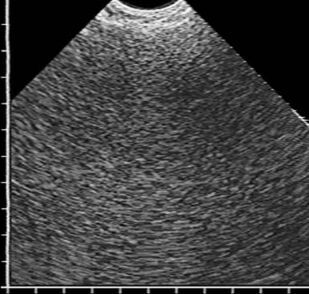

Ультразвуковая диагностика воспалительных заболеваний легких

В учебном пособии в практическом аспекте изложены вопросы ультразвуковой диагностики воспалительных заболеваний легких: приведена методика исследования и нормальная эхографическая картина грудной клетки, подробно освещена ультразвуковая семиотика и дифференциальная диагностика пневмоний, в том числе деструктивных, абсцессов и гангрены легкого, для каждого из них выделены диагностически значимые эхопризнаки. Впервые представлена эхосемиотика пневмоний в зависимости от степени тяжести воспалительной инфильтрации, а также абсцессов легкого в зависимости от эффективности спонтанного дренирования его полости бронхами. Пособие иллюстрировано большим количеством эхограмм, отображающих основные диагностические признаки рассматриваемых заболеваний.